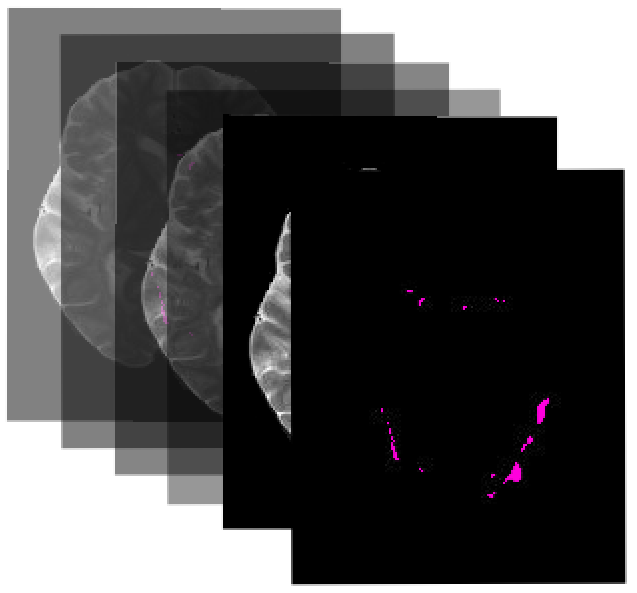

Many automatic machine learning models developed for focal pathology (e.g. lesions, tumours) detection and segmentation perform well, but do not generalize as well to new patient cohorts, impeding their widespread adoption into real clinical contexts. One strategy to create a more diverse, generalizable training set is to naively pool datasets from different cohorts. Surprisingly, training on this \it{big data} does not necessarily increase, and may even reduce, overall performance and model generalizability, due to the existence of cohort biases that affect label distributions. In this paper, we propose a generalized affine conditioning framework to learn and account for cohort biases across multi-source datasets, which we call Source-Conditioned Instance Normalization (SCIN). Through extensive experimentation on three different, large scale, multi-scanner, multi-centre Multiple Sclerosis (MS) clinical trial MRI datasets, we show that our cohort bias adaptation method (1) improves performance of the network on pooled datasets relative to naively pooling datasets and (2) can quickly adapt to a new cohort by fine-tuning the instance normalization parameters, thus learning the new cohort bias with only 10 labelled samples.

翻译:为焦点病理学(如损伤、肿瘤)检测和分解而开发的许多自动机器学习模型效果良好,但并不普遍适用于新的病人组群,妨碍他们被广泛采用到真正的临床环境中。创建更多样化、更普遍的培训组的战略是天性地汇集不同组群的数据集。奇怪的是,关于这一类组群的训练不一定增加,甚至可能降低整体性能和模型一般性,因为存在影响标签分布的群群群偏见。在本文件中,我们提议了一个通用的缝合框架,以学习和核算多源数据集组群偏向,我们称之为源-受限制的正常化(SCIN ) 。 通过对三种不同规模、大型、多扫描器、多中心多重分解(MS)临床试验 MRI 数据集进行广泛的实验,我们表明我们的群群偏差适应方法(1) 改善了与天真的集数据集相对的集合数据集网络性能,(2) 通过微调的定置像机群,只能通过精确的定型模型来迅速适应新的组群群。